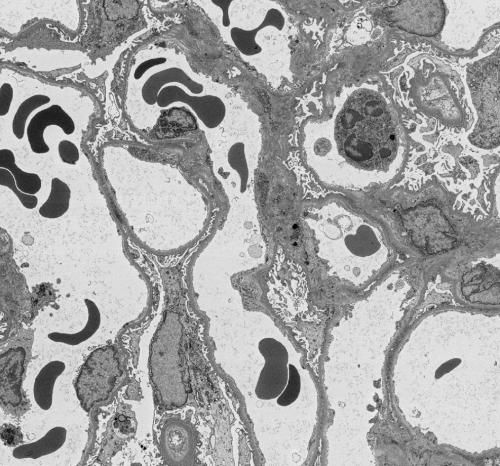

In this project you'll get to see some very high resolution images of kidney tissue, like this one!

To make sense of the images taken by the electron microscope we must carefully analyse them. To extract meaning from the images we segment the features we’re interested in, which means to draw around the bits of the image that we want to study. We need your help with this task – to colour in different parts of the image. In this Etch A Cell project, we would like you to help us to study immune cells in kidney tissue.

In this project we need you to spot and draw around immune cells, which you can see in this image outlined in green (for more examples, see our immune cell gallery in the Field Guide tab which you can find on the right hand side of your screen)

Our current understanding of rejection comes from examining biopsies of the transplant using a standard light microscope, and from analysing expression of genes in biopsy tissue. Antibodies and other molecules gather in the small blood vessels of the kidney and attract a variety of immune cells. These immune cells get 'activated' and damage the lining of the blood vessels, causing thickening of the vessel walls. Eventually, this prevents the kidney from filtering fluid and waste from the blood.